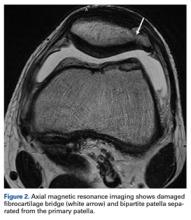

A magnetic resonance imaging (MRI) series was ordered for further evaluation of the soft tissues (Figure 2). There was bony edema in the anteromedial aspect of the distal femur. The visualized patella showed no evidence of fracture, though there was evidence of disruption through the fibrous attachments of the bipartite patella fragment. Physical therapy (range-of-motion exercises, quadriceps sets, and stationary bicycling) was initiated. By 6 weeks, the patient’s discomfort had resolved, and he resumed on-ice activities as tolerated.Two years later, the patient returned with left AKP, again localized to the lateral aspect of the patella, over the bipartite fragment. The pain was significant with compression. Given the patient’s history, arthroscopic excision of the bipartite patella was recommended. After discussing all treatment options, the patient elected to proceed with the surgery.